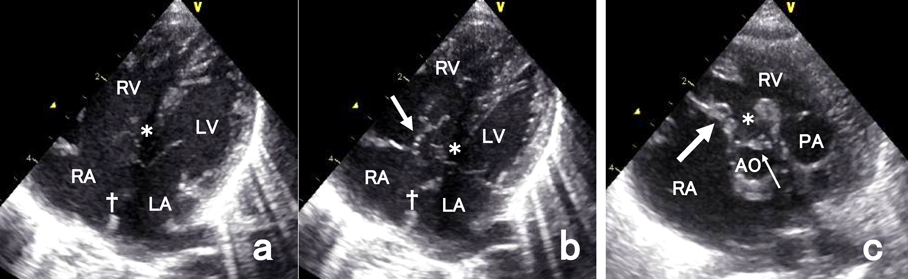

Fig. 3 Echocardiogram shows thick and redundant valves in patients with trisomy 18

(a) Four chamber view in diastole shows a perimembranous inlet defect of the ventricular septum (*) and a defect of the atrial septum (†). (b) Four chamber view in systole shows a redundant tricuspid valve (arrow). (c) Another patient with tetralogy of Fallot. Parasternal short axis view shows thick and redundant tricuspid valve (large arrow) and aortic valve (small arrow). There is a large defect of the ventricular septum (*). RA: right atrium, LA: left atrium, RV: right ventricle, LV: left ventricle, AO: aorta, PA: pulmonary artery